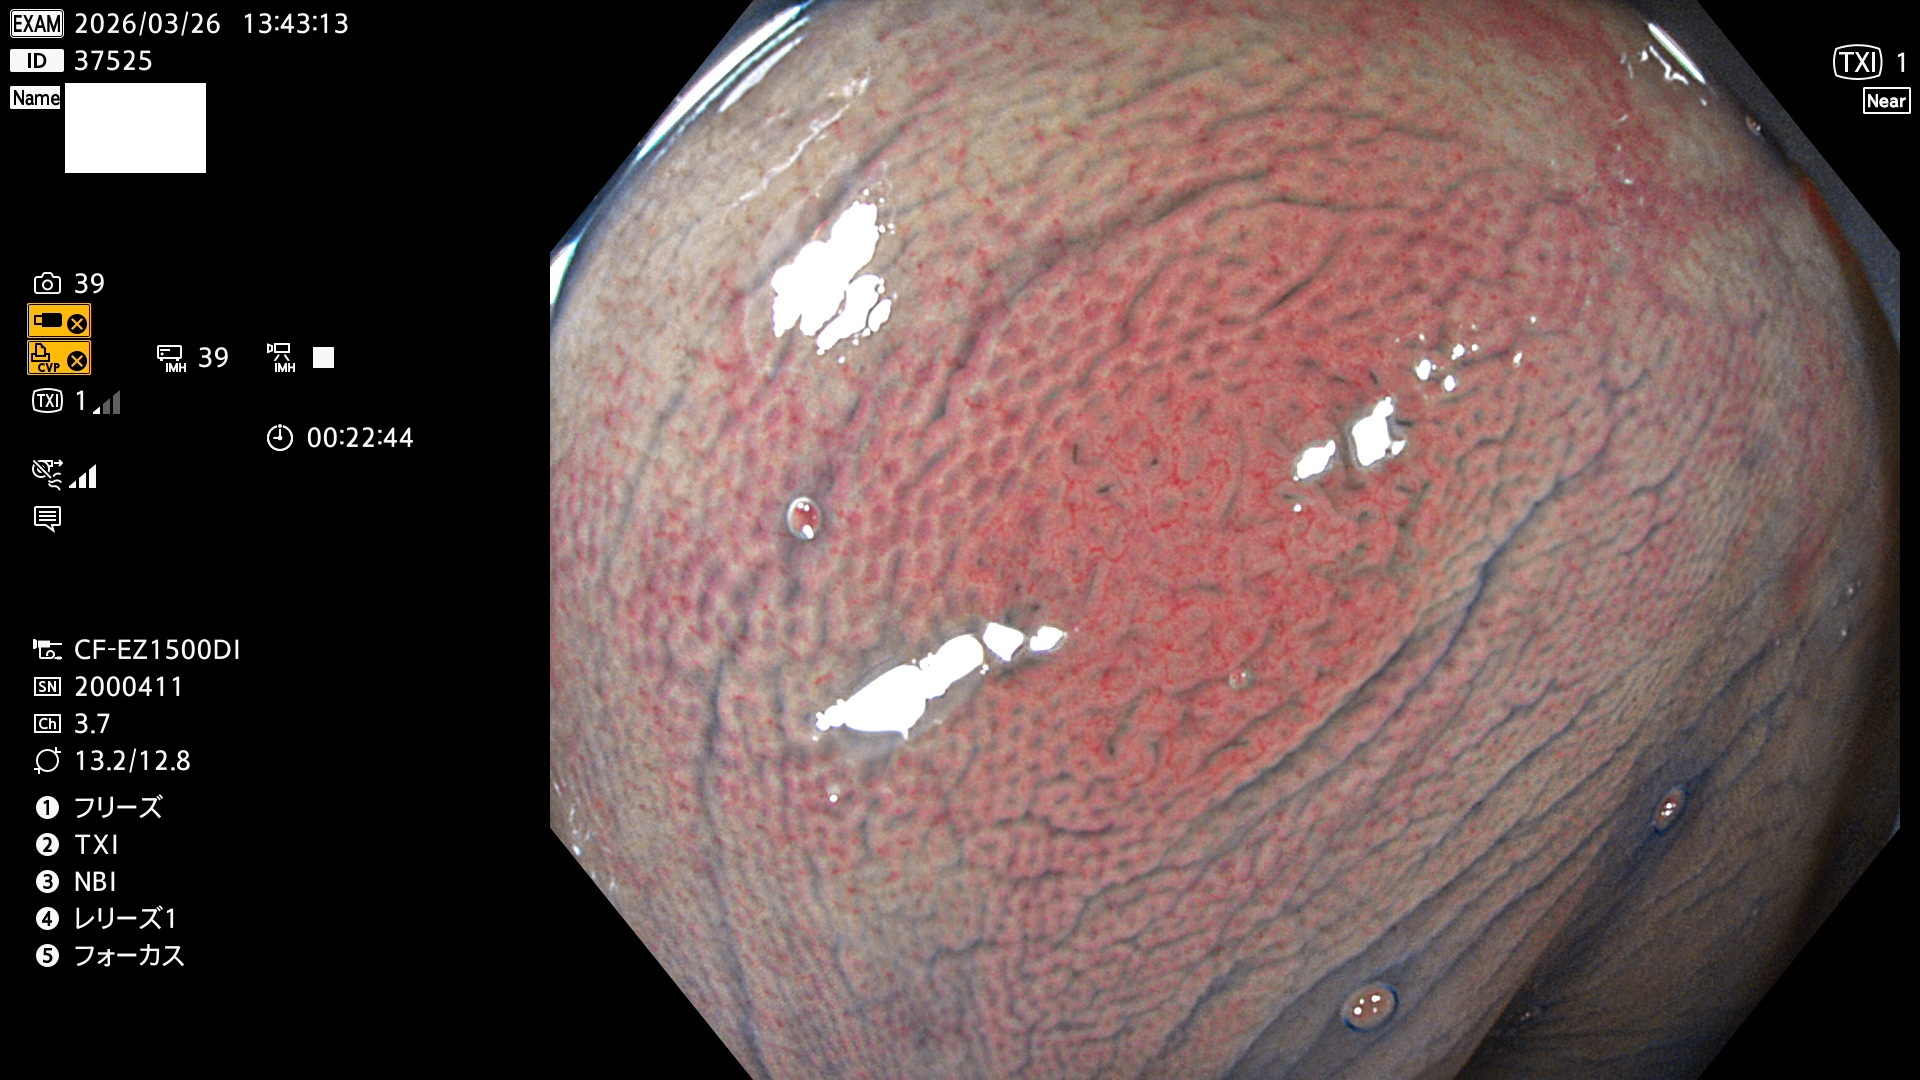

完全に平坦な物をUb、陥凹している物をUcと呼びます。Ubは認識が困難で、Ucはびらん(炎症)と紛らわしいために見落とされやすく、「内視鏡後・大腸癌」の原因になります。

専門的)Uc=De Novo癌? 内視鏡の解像度が低かった時代、このような説もありました。しかし今日の高精度内視鏡では良性の微小なUc型腺腫(APC遺伝子異常の腺腫)が日常的に見つかります。Ucこそが多段階発癌(Adenoma-Carcinoma Sequence)のMain Routeです。

毎週の検査(木・金・土・日)に発見されたUbとUc型・腺腫を、その週の日曜の夜にUPし1週間、提示します。

2026年3月26日〜3月29日の4日間(40件)4個 (Uc_ADR=4個/40人=10%)